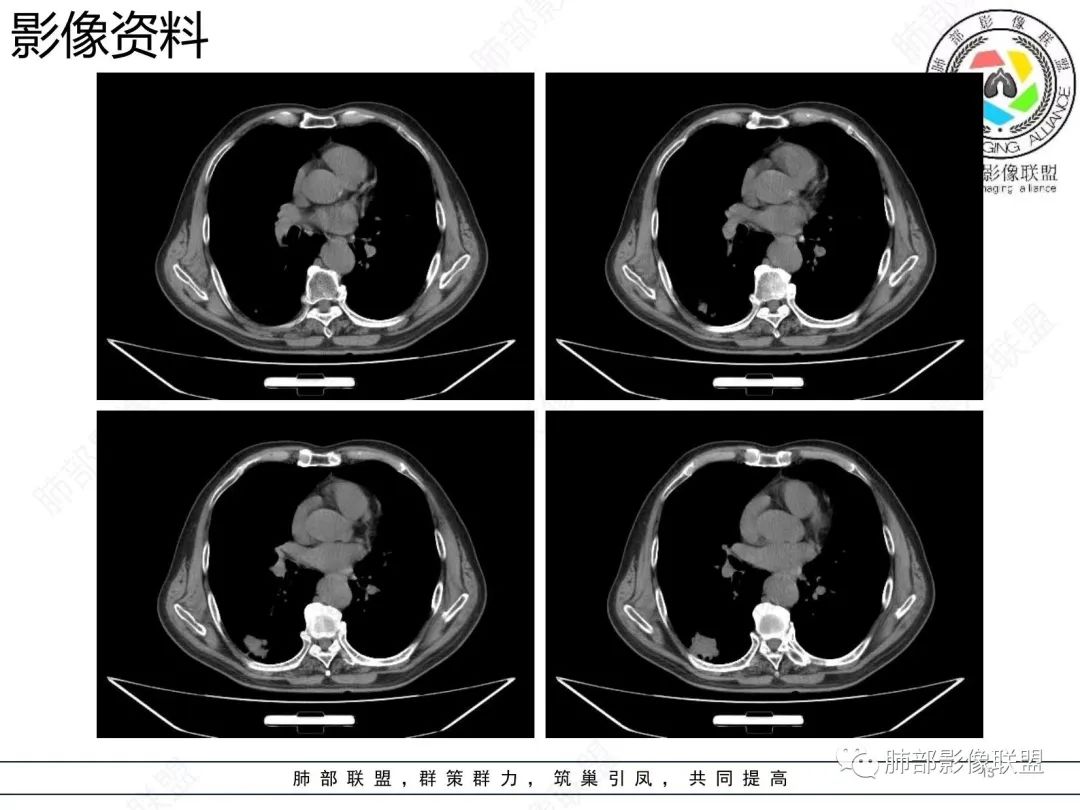

老年男性,右肺下叶混合磨玻璃密度结节,可见血管弯征,首先考虑肺腺癌。

右肺下叶背段不规则结节,边界欠清,可见少许晕征,另见胸膜凹陷征及血管弯,考虑腺癌,鉴别隐球菌。

右肺下早不规则结节,周围少许磨玻璃晕,胸膜有牵拉凹陷,虽然部分边界平直,但血管受牵拉弯曲,首先还是考虑肿瘤,腺癌

右肺下叶背段斑片影,边缘平直、局部膨隆,可见磨玻璃密度影,界清,胸膜牵拉,良恶性需要进一步鉴别,倾向隐球,鉴别粘液腺癌。

老年男性,右肺下叶胸膜下结节,边缘见清晰磨玻璃密度影及少许索条,支气管进入后截断,周围血管弯,考虑腺癌,鉴别隐球菌

右肺下叶胸膜下混合密度结节,分叶、毛刺,磨玻璃边界尚清晰,血管集束,支气管进入阻断,考虑腺癌

右肺下叶背段胸膜下肿块,边缘不规则,分叶,毛刺,有磨玻璃,边界清,近肺门侧见血管聚集,支气管进入后闭塞,右肺下叶肺静脉牵拉扭曲。诊断,支持腺癌

老年患者,无呼吸道相关症状,肺部影像学表现:胸膜下占位,有结节融合趋势,内有低密度灶。考虑隐球菌,鉴别腺癌。

胸膜下结节,与胸膜平行,多结节融合,边缘模糊,直边征,考虑炎性肉芽肿,隐球,腺癌

右肺下叶背段实性结节,边缘分叶,较平直,长轴平行胸膜,胸膜增厚,考虑炎性假瘤,隐球菌,鉴别腺癌。

混合性磨玻璃结节,边界清晰,血管打弯,考虑腺癌,鉴别炎性肉芽肿病变。

老年男性,体检发现,无症状,右肺下叶背段肿块影,边缘清楚,无卫星灶,棘状突起,毛刺征,血管集支束,空泡征,考虑恶性肿瘤。

老年男性,体检发现。右肺下叶混合磨玻璃结节,渗漏征,短毛刺,血管集支束,空泡,考虑腺癌。

老年男性右肺下叶靠近胸膜一不规则混合密度影,周围有渗出,内见支气管扩张,考虑炎性病变隐球鉴别腺癌

老年男性 右肺下叶胸膜下见一团状实性病灶+边缘磨玻璃,边缘形态不规则,,局部有平直,长轴平行于胸膜面,整体收缩力偏弱,邻近胸膜面轻度增厚,纵隔窗显示病灶内可见支气管充气,考虑炎性肉芽肿,隐球菌可能,鉴别黏液腺癌。

右肺下叶实行病灶,边缘部分有边界清晰的磨玻璃影,实变明显层面,可见平直。考虑腺癌

右下肺近胸膜病变,周围可见磨玻璃影,界限无法判断清楚?模糊?。考虑右下肺占位:真菌感染?腺癌?淋巴瘤?

右肺下叶胸膜下结节,边界清楚毛玻璃,有分叶、毛刺、血管集束及胸膜增厚,考虑肉芽肿性病变,鉴别于腺癌

右肺下叶实性病灶,局部平直,考虑炎性病变,隐球菌可能

胸膜下结节,长轴与胸膜平行,边缘模糊,直边征胸膜凹陷牵拉不明显,考虑炎性肉芽肿,隐?鉴别腺癌。

右肺下叶后基底段胸膜下斑块影,边缘清楚,有平直和膨隆特点,周围清楚GGO,较模糊(似清非清,邻近见多发纯GGO结节,以肺腺泡分布,主体病灶与胸膜平行,收缩力弱,边缘见支气管充气征,首诊断炎性肉芽肿,抗炎治疗和查下隐球荚膜抗原两方面进行,另取旧片对比,与粘液腺Ca鉴别,最后经皮肺穿刺病理诊断!

上面这些征象存在炎性病变可能,我先考虑炎性病变——隐球,这样的血管弯在肺隐球菌病里也出现过。腺癌尤其是粘液腺癌也不敢排除。建议完善血隐球菌荚膜抗原、经皮肺穿刺活检等检查。

结节型粘液腺癌,具有血管弯,支气管截断,磨玻璃边界清楚等恶性征象,同时磨玻璃内部较糊,似清非清,不符合普通腺癌附壁生长特点,更像局限的粘液成分。收缩力不强,胸膜局部微积液,内部小空洞(考虑局部粘液排除形成),所以考虑结节型粘液腺癌。